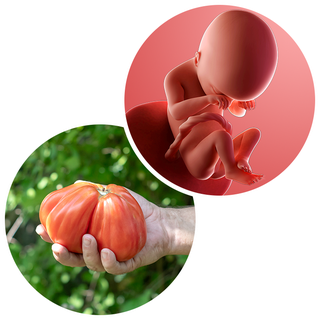

What does my baby look like?

Your baby, or foetus, is around 15.3cm long from head to bottom. That's approximately the size of a beef tomato.